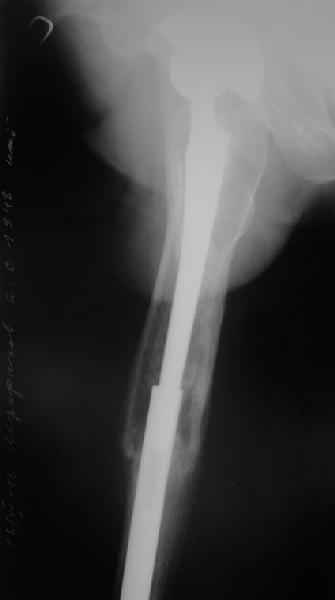

Пациента удалось осмотреть недавно. Достигнутый результат сохраняется. Перелом бедра сросся. Конечность опорная и безболезненная, ходит без трости. Ножка, похоже, реинтегрировалась, как и надеялись. Снимки и фото в приложении. Комментарии приветствуются.

Надо ли что-то делать дальше, как полагаете? Убрать винты? Убрать "удлинитель ножки"? Или оставить все, как есть? Спасибо заранее.